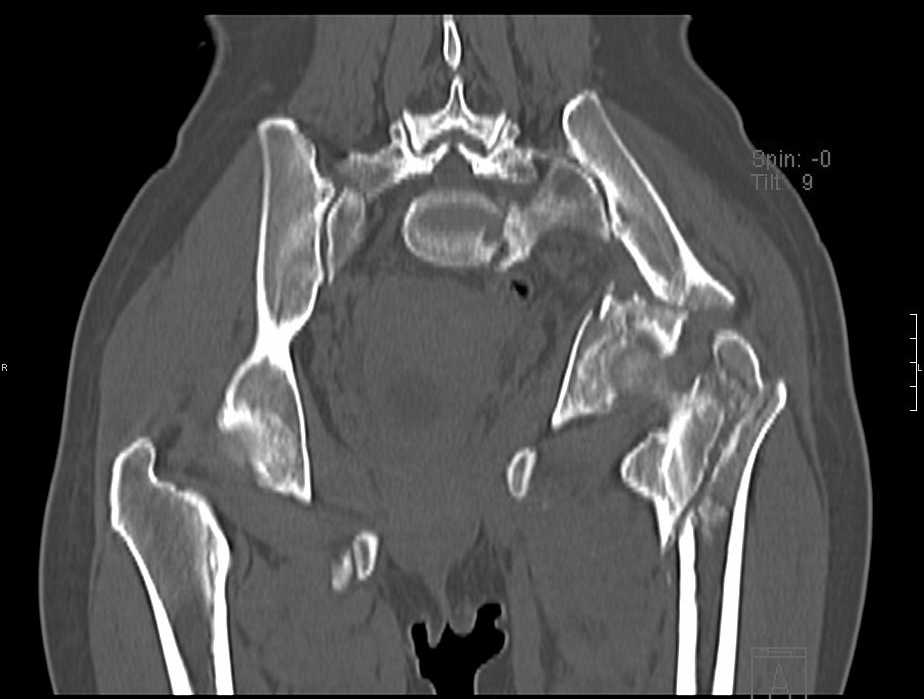

Больная 43 года (промышленный альпинист), 28.07.08 в результате падения с 5 этажа получила политравму:

Перелом свода и основания черепа. Вертикально-нестабильное повреждение таза, осложнённое разрывом мочевого пузыря. Чрезвертельный перелом левого бедра. Перелом правой таранной кости, переломовывих правой кубовидной кости. Тупая травма живота, разрыв печени, ушиб почек. Забрюшинная гематома. В день травмы - лапаротомия, ушивание ран печени. Разрыв мочевого пузыря не диагностирован. Течение болезни осложнилось развитием мочевого затёка и обширной пред- и забрюшинной флегмоны, сформировался свищ мочевого пузыря. 19.8.2008 вскрытие, дренировние флегмоны, ревизия мочевого пузыря, обтурация мочевого свища (свищ закрылся в октябре), 1.10.2008 некрэктомия, пластика по Шеде-Лидскому правой кубовидной кости. По результатам КТ диагностирован рак правой почки (диагностическая находка), 8.10.2008 нефрэктомия справа.

Имеется вертикальное смещение левой половины таза с выраженным отведением крыла (клинически подвижности нет), несросшийся низкий двухколонный перелом левой вертлужной впадины с потерей конгруэнтности, укорочение около5 см, застарелый разрыв лонного сочленения, неправильно сросшиеся переломы обеих ветвей правой лонной кости с укорочением, патологическая подвижность лоно-седалищного фрагмента слева. Правая нижняя конечность неопорна, несмотря на то, что лежа прямую ногу поднимает, ходит на левой ноге (ортопедическая обувь) с костылями, справа тазобедренный ортез. Седалищные нервы работают.Урологи отпустили больную на 6 мес.